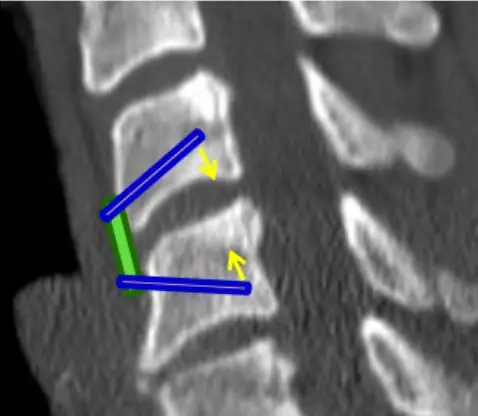

![]()

去除前部和后部骨赘(头侧和尾侧)以形成用于插入椎间融合器的平行通道。

用刮匙和/或锉刀进行终板准备以增强椎间融合。

前板需选择适当的尺寸,避免过长延伸影响到相邻的椎间盘空间。

矢状面上将螺钉置于“发散”状态以使压力传递到椎间植入物上。